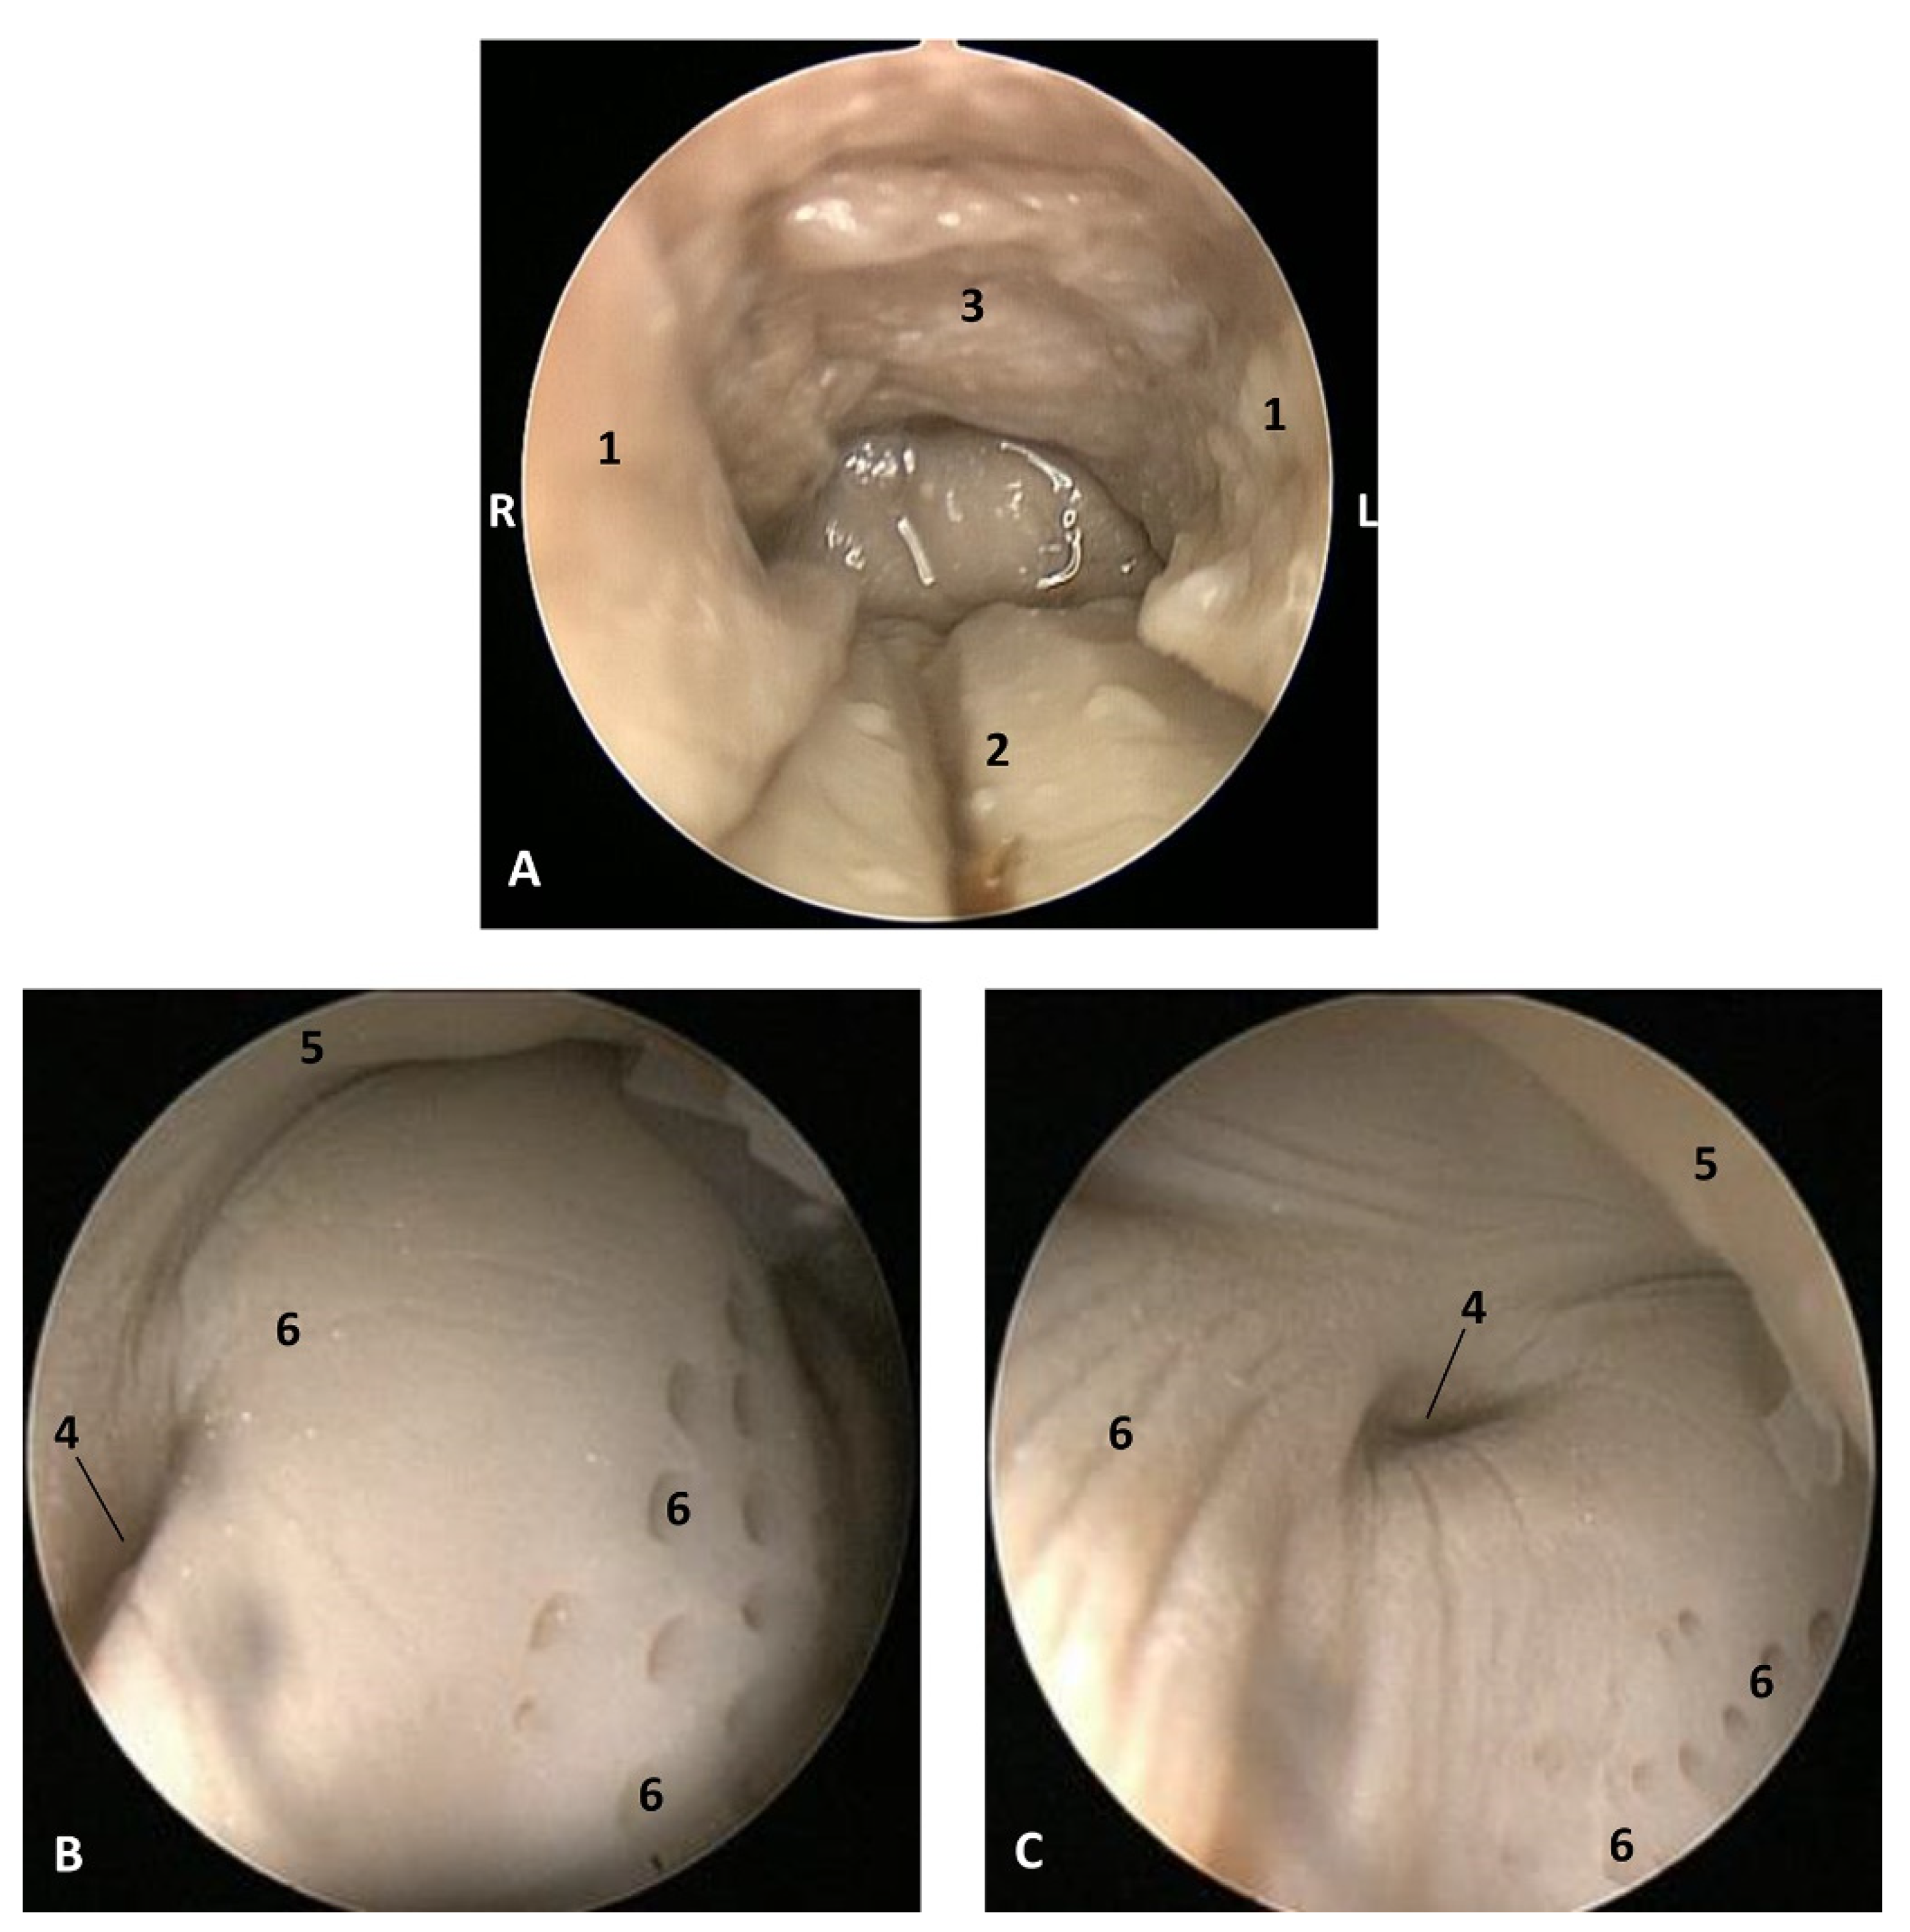

In the youngest newborn Stenella coeruleoalba (scoce1), all teeth are covered by gums. Teeth eruption can be seen in the two older newborn specimens (scomu1 and scomu2) where the caudal teeth start to erupt, but the rostral teeth are covered by gums and the incisive teeth are not well developed. Also, the marginal papillae are well developed and decrease progressively towards the root. (Figure 10).

Figure 10.

Endoscopic images of the oral cavity. In the different images, the arrow points to the tip of the mouth. L (Left) R (Right). (A) Hard palate. (B) Tongue. (C–F) Tongue, oral cavity proper and prefenular space. newborn, scumu2. (G) Deep dissection of the newborn dolphin head after removing skin and partial section of the right mandible. Observe that rostral teeth during lactation period do not erupt to protect mother’s nipple. newborn, scoce1. (H) Detailed image of the marginal papilla and teeth without gum covering the clinic crown. A palatal raphe in hard palate is present. newborn, scomu1. 1, Upper lip; 2, Lower lip; 3, Incisive papilla; 4, Labial vestibule; 5, Gums; 6, Hard palate; 7, Palatine raphe; 8, Tongue: tip; 9, Tongue: border; 10, Tongue: marginal papilla; 11, Tongue: dorsum (middle tongue groove); 12, Tongue: ventral part; 13, Lingual frenulum; 14, lateral sublingual recess; 15, Lateral sublingual folds; 16, Tongue: root; 17, Teeth roots; 18, Angulus oris.

3.1.2. MRI Study

The T2 MRI image of the oral cavity in this Delphinus delphis (dde11) shows that the maxillary bone is medium hyperintense with respect to the hypointense hard palate. The superficial mucosa of tongue is slightly hyperintense with respect to the hypointense depressor, protractor and retractor muscles of the tongue. A hyperintense stratum under the tongue muscles is probably due to the high rate of irrigation of these muscles. We observed that non-erupted teeth can be seen under the gums (Figure 11).

Figure 11.

Images of the oral cavity. MR sagittal images is oriented so that the rostral is to the right. (A) T2 FrFSE sagittal plane. 6 months, dde8. Image of the oral cavity. (B) T2 FrFSE sagittal plane. Quadknee coil. 8 months, dde11. 1, Teeth (under gum); 2, Tongue: body; 3, Maxillary bone; 4, Hard palate; 5, Soft palate; 6, Tongue: apex; 7, Tongue: root; 8, Mandibles; 9, Pterygoid and palatine bones.

3.1.3. Histological Study

Vestigial incisive papillae appear with a keratinized pseudostratified epithelium. Conduits arriving at papilla were not seen, nor was the vomeronasal organ Delphinus delphis fetus (dde14). Abundant lymphatic vessels were observed in the dermis. Developing teeth were observed covered by gum tissue. The histological structure of teeth shows the inner dentin, covered by enamel and all parts (crown, neck, and root) covered by cementum. The sublingual lateral folds have a mucosa with abundant vessels and mucous glands while neither the sublingual caruncule nor the orobasal organ were observed (Figure 12 and Figure 13).

Figure 12.

(A,B) Histological study of the oral cavity. (A–C) Hard palate: incisive papilla. (D) Tooth. (E) Oral cavity proper: sublingual lateral fold. (F) Tongue: root. 10 months, dde14. 1, Epidermis; 2, Papillary stratum; 3, Nervous tissue; 4, Connective tissue; 5, Lymphatic vessels; 6, Bony tissue; 7, Dental structure initial development transverse sectioned; 8, Dental structure development sagittal sectioned; 9, Dental papilla; 10, Dentin; 11, Enamel; 12, Cementum; 13, Venous vessels; 14, Striated muscle; 15, Mucous glands.

Figure 13.

(A,B) Histological study of the oral cavity. (A) Sublingual lateral fold: pigmented epithelium in basal stratum (*). (B) Tooth. (C,D) Tongue: root. 7.5 months, dde10. 1, Epidermis; 2, Papillary stratum; 3, Mucous glands; 4, Secretor duct; 5, Striated muscle: proper muscle tongue; 6, Dental papilla 7, Dentin; 8, Enamel; 9, Cementum.

The sublingual lateral fold showed a pigmented epithelium at its basal stratum. The tongue shows a striated muscle base and abundant sub-epithelial mucous glands are visible, along with their secretory ducts (Figure 13).

In an adult Stenella coeruleoalba (scomu6), the incisive papilla showed a well-developed papillary stratum. The dermis contains abundant fat tissue and nests of epithelial ducts in regression (Figure 14A,B). The lateral sublingual recess has a keratinized epithelium with mucous glands and a well-developed papillary stratum (Figure 14).

Figure 14.

(A,B) Histological study of the oral cavity. (A,B) Hard palate: incisive papilla. (C,D) Oral cavity proper: sublingual lateral fold. Adult, scomu6. 1, Epidermis; 2, Papillary stratum; 3, Corneum stratum; 4, Fat tissue; 5, Connective tissue; 6, Remains of epithelial duct; 7, Lymphatic vessels.